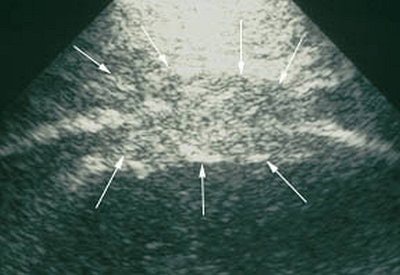

Herth recommended using a highly soluble transducer (5 MHz) to look at pathological findings in the chest wall of mesothelioma patients. In advance stages of the disease, tumor infiltration of the lung tissue will appear as echo-poor, oblong structures along the ventilated lung. Pleural metastases are also echo-poor, or moderately echo-close, and present as roundish, small, knotty, or laminar processes with irregular delimitation.

| A Brustwand echocardiogram depicting infiltrating carcinoma. |

"Pleural mesothelioma presents sonographically as an irregularly limited, echo-poor, knotty, or planar widening along the pleura," Herth wrote in Lung Cancer. "An increase in the pleural thickness, however, suggests the likelihood of malignancy. A widening of the pleura of more than 1 cm is considered highly indicative of the presence of malignant tumor" (August 2004, Vol. 45:1 supplement, pp. S63-67).